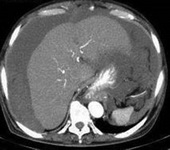

萬芳醫院從2000年開始嘗試第一例的腫瘤減量手術合併腹腔熱化療,治療胃癌合併有腹腔轉移的病例,並於2002年開始常規的施行此項治療, 隨後並擴展到其他各式各樣的癌症。

Wan-Fang Hospital started to perform CRS (cytoreduction surgery) plus HIPEC (hyperthermic intraperitoneal chemotherapy) at 2000, to treat the first case of gastric cancer with peritoneal metastasis. Since 2002, it became a regular procedure and treat many kinds of cancers at the present.